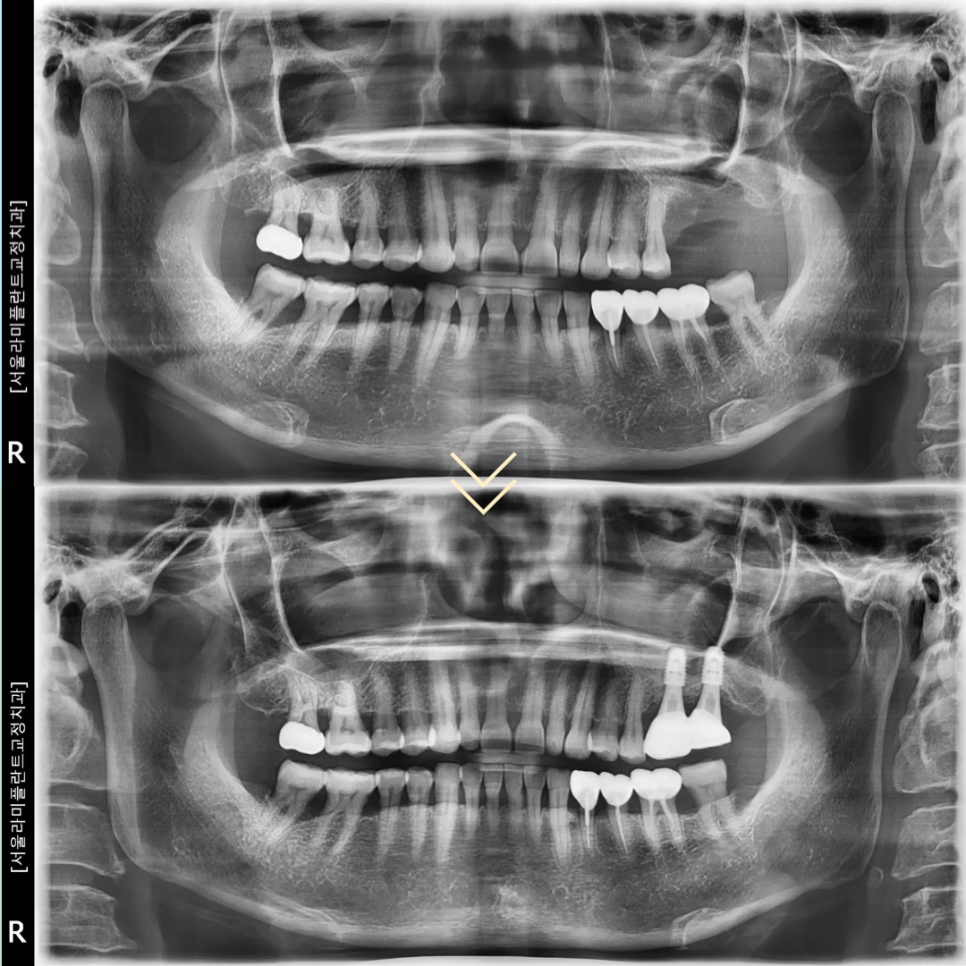

치료 기간은 2024년 6월 10일부터

2025년 4월 14일까지로 약 10개월간

이번 증례의 환자는 50대 여성으로

지인의 소개를 통해 내원하였습니다.

보철완료까지 전체 치료 기간은

약 10개월이 소요되었으며

파괴되었던 치조골이 점차 회복되면서

임플란트가 안정적으로 자리

잡는 과정을 확인할 수 있었습니다.